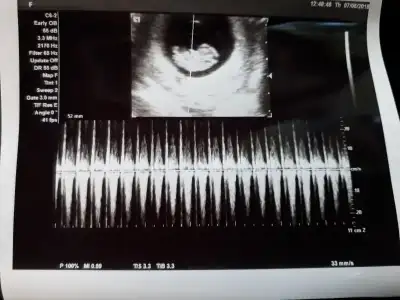

Bebeğimi gördükk. :) 9+4'üm bugün. Haftasıyla uyumlu, kalbi gümbür gümbür atıyor eskisine göre maşallah. :) 20 gün önce hiçbir şey belli olmuyorken şimdi elleri, kolları, kafası... Doktor 2 hafta sonra 2'li test için çağırdı.